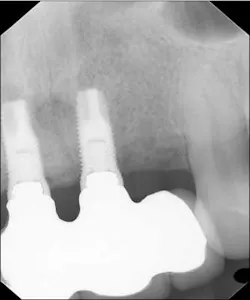

A 43-year-old female with a noncontributory medical history taking no medication and having no known food/drug allergies presented to my general dental office with a chief complaint of having “loose teeth with an underbite.” Clinically, she had generalized, moderate, chronic periodontal disease and was missing teeth Nos. 8 through 10. She had a Class III malocclusion with pathologic flaring of her remaining anterior teeth. She had both vertical and horizontal tissue loss in the No. 8 through 10 region. The patient wore a transitional partial denture to replace the anterior missing teeth that was placed in edge-to-edge occlusion by her previous dentist. (Fig. 1) She did not like having a removable prosthetic and desired a fixed option in the form of implants to replace her missing teeth. I sent her to the periodontist for a periodontal consult for her remaining dentition and dental implants to replace her missing front teeth.